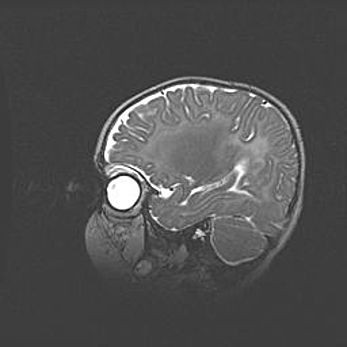

Мальформация Денди-Уокера. Киста задней черепной ямки.

Агенезия мозолистого тела.

Возраст: 2,5 месяца

Вес: 2420 г

Пол: женский

Окружность головы: 37 см

Срок гестации: 32 недели

Мальформация Денди—Уокера — редкий вид патологии ЦНС, представляющий собой врожденный порок развития каудального отдела ствола и червя мозжечка, ведущий к неполному раскрытию срединной (Мажанди) и латеральных (Лушка) апертур IV желудочка мозга. Для этогно синдрома характерна триада симптомов: гипотрофия червя мозжечка и/или полушарий мозжечка, кисты задней черепной ямки, гидроцефалия различной степени. В 70% случаев порок сочетается и с другими аномалиями головного мозга, в частности с агенезией мозолистого тела.